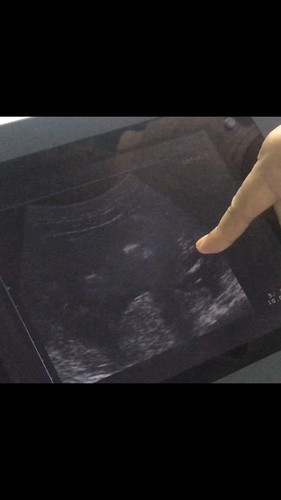

ไปซาวด์มาวันนี้ได้ลูกสาวคือทุกคนรอบข้างพูดกันหมดว่าได้ผู้ชายเพราะโทรมมาก ผอม สิวขึ้นช่วง2 เดือนแรก ตอนนี้ 5 เดือนกว่าคือหน้าใสขึ้นเปร่งปลั่งขึ้น ดีใจมาก ??

ของเราตอนท้องไตรมาสแรกหน้ามีแต่สิวค่ะ กังวลว่าจะได้ชาย พอไตรมาสที่สองหน้าใสกริ๊ง สิวหายเลยค่ะ ผลอัลตร้าซาวด์ได้ ลูกสาวจ้า

บ้านนี้ก็โทรมจ้า ไม่แต่งหน้า สิว ขึ้น วันนี้หมอคอนเฟริมแล้ว ผู้หญิง100%จ้า 26+1d คนรอบข้างก็ทักว่าเป็นผู้ชายเหมือนกัน